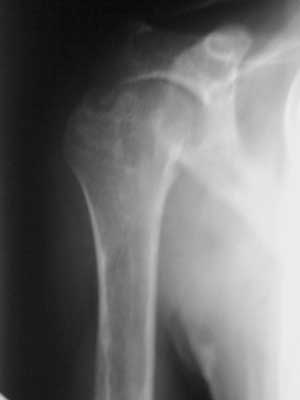

标题: X7099:27岁、右肩疼痛三月余。

图像欠清晰,位置不标准,影响了诊断。仅能提示肱骨头及关节盂形态不自然,考虑与发育有关。

看不清,肱骨头有破坏?软骨母?tb?

考虑右肩关节结核;建议行ct扫描检查。

肱骨头、关节盂似有骨质破坏,肱骨头细小,考虑肩关节结核可能。

右肱骨头及肩盂不规则骨质破坏,密度不均匀减低,周围未见骨质明显硬化,病变跨关节发生,肩关节结核可能性大。

右肱骨头骨质破坏,边缘稍硬化,周围结节高密度影,骨结核可能,建议ct

右肱骨头骨质破坏,骨结核可能性大。